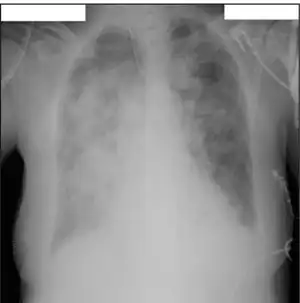

| File:Ijms-18-00020-g001.B.png | |

| Virion structure of influenza B virus | |